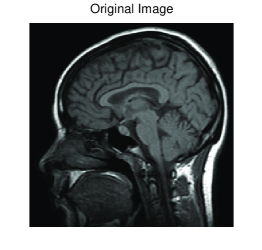

We conclude with an illustration of the performance of the GCV-Arnoldi approach on a 2D image deblurring problem which consist in recovering the original image from a blurred and noisy observed image.

Let be a two dimensional image. The vector of dimension obtained by stacking the columns of the image represents a blur-free and noise-free image. We generate an associated blurred and noise-free image by multiplying by a block Toeplitz matrix with Toeplitz blocks, implemented in the function blur.m from the Regularization Tools [15]. This Matlab function has two parameters, band and sigma; the former specifies the half-bandwidth of the Toeplitz blocks and the latter the variance of the Gaussian point spread function. The blur and noise contaminated image is obtained by adding a noise-vector , so that . We assume the blurring operator and the corrupted image to be available while no information is given on the error , we would like to determine a restoration which accurately approximates the blur-free and noise-free image .

We consider the restoration of a corrupted version of the test image mri.png. Contamination is by 1% white Gaussian noise and space-invariant Gaussian blur. The latter is generated as described above with blur parameters band=7, sigma=2, so that the condition number of is around . Figure 6 displays the performance of the AT-GCV. On the left the blur-free and noise-free image, on the middle the corrupted image, on the right the restored image. From top to bottom the image in original size and two different zooms. The regularization operator is defined as (cf. [7])

where is the discretized first derivative with a zero row at the bottom (cf. also [17, §5]).

The experiment has been carried out using Matlab 7.10 on a single processor computer (Intel Core i7). The result has been obtained in 5 iterations of the Arnoldi algorithm, in around seconds. Many other experiments on image restoration have shown similar performances.